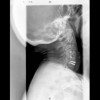

Columna cervical